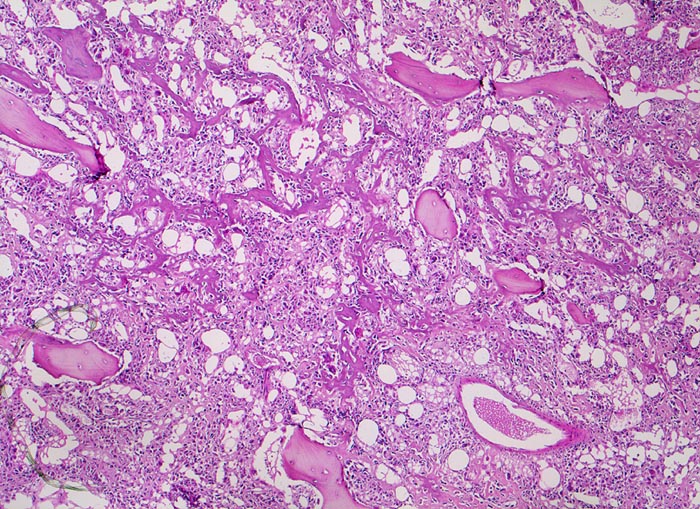

Das histologische Bild kann deutlich variieren. Der Tumor kann beispielsweise nur ganz fokal Osteoid produzieren und ansonsten wie ein undifferenziertes pleomorphes Sarkom aussehen, er kann aber auch massenhaft Knorpelmatrix bilden und/oder Riesenzellen enthalten. Der Nachweis von neoplastischem Osteoid ist entscheidend in der Abgrenzung von anderen Sarkomtypen.

• Tibiametaphyse mit angrenzendem Weichteilgewebe.

• Das Sarkom infiltriert diffus den spongiösen Knochen der Diaphyse und hat präexistente Knochenbälkchen verdrängt.

• Der Tumor hat die Korticalis destruiert und infiltriert die angrenzende Skelettmuskulatur.

• Der Tumor besteht aus neugebildetem bereits verkalktem Knochen oder einem Netzwerk von primitiven Osteoidtrabekeln. Entlang oder innerhalb der Osteoidtrabekel lokalisierte polymorphe Tumorzellen mit ausgeprägten Kernatypien und zahlreichen Mitosen. Leicht verwaschene Kernstrukturen als Folge der Gewebsentkalkung.